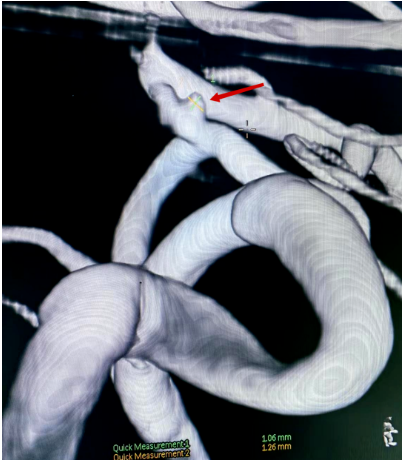

造影术中见前交通有一囊性凸起,结合蛛网膜下腔出血重、临床症状进展快的特点,考虑前交通血泡样动脉瘤,血泡样动脉瘤多见于颈内动脉床突段,而前交通血泡样动脉瘤极为罕见。该类动脉瘤瘤壁菲薄,仅被血凝块、纤维组织或动脉外膜覆盖,缺乏内膜、弹力层、中层及胶原组织,动脉瘤再次破裂性大,若不手术干预,患者再发出血及死亡率高,因此该类病人总体预后差。我院神经外科本着“厚德、至善、精业、进取”的精神,神经外科医师团队迎难而上开展了微创介入手术治疗。

(图2 DSA血管3D成像)